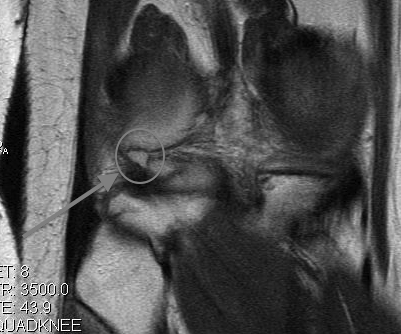

MRI

2 x Osteochondral Fragments in Notch